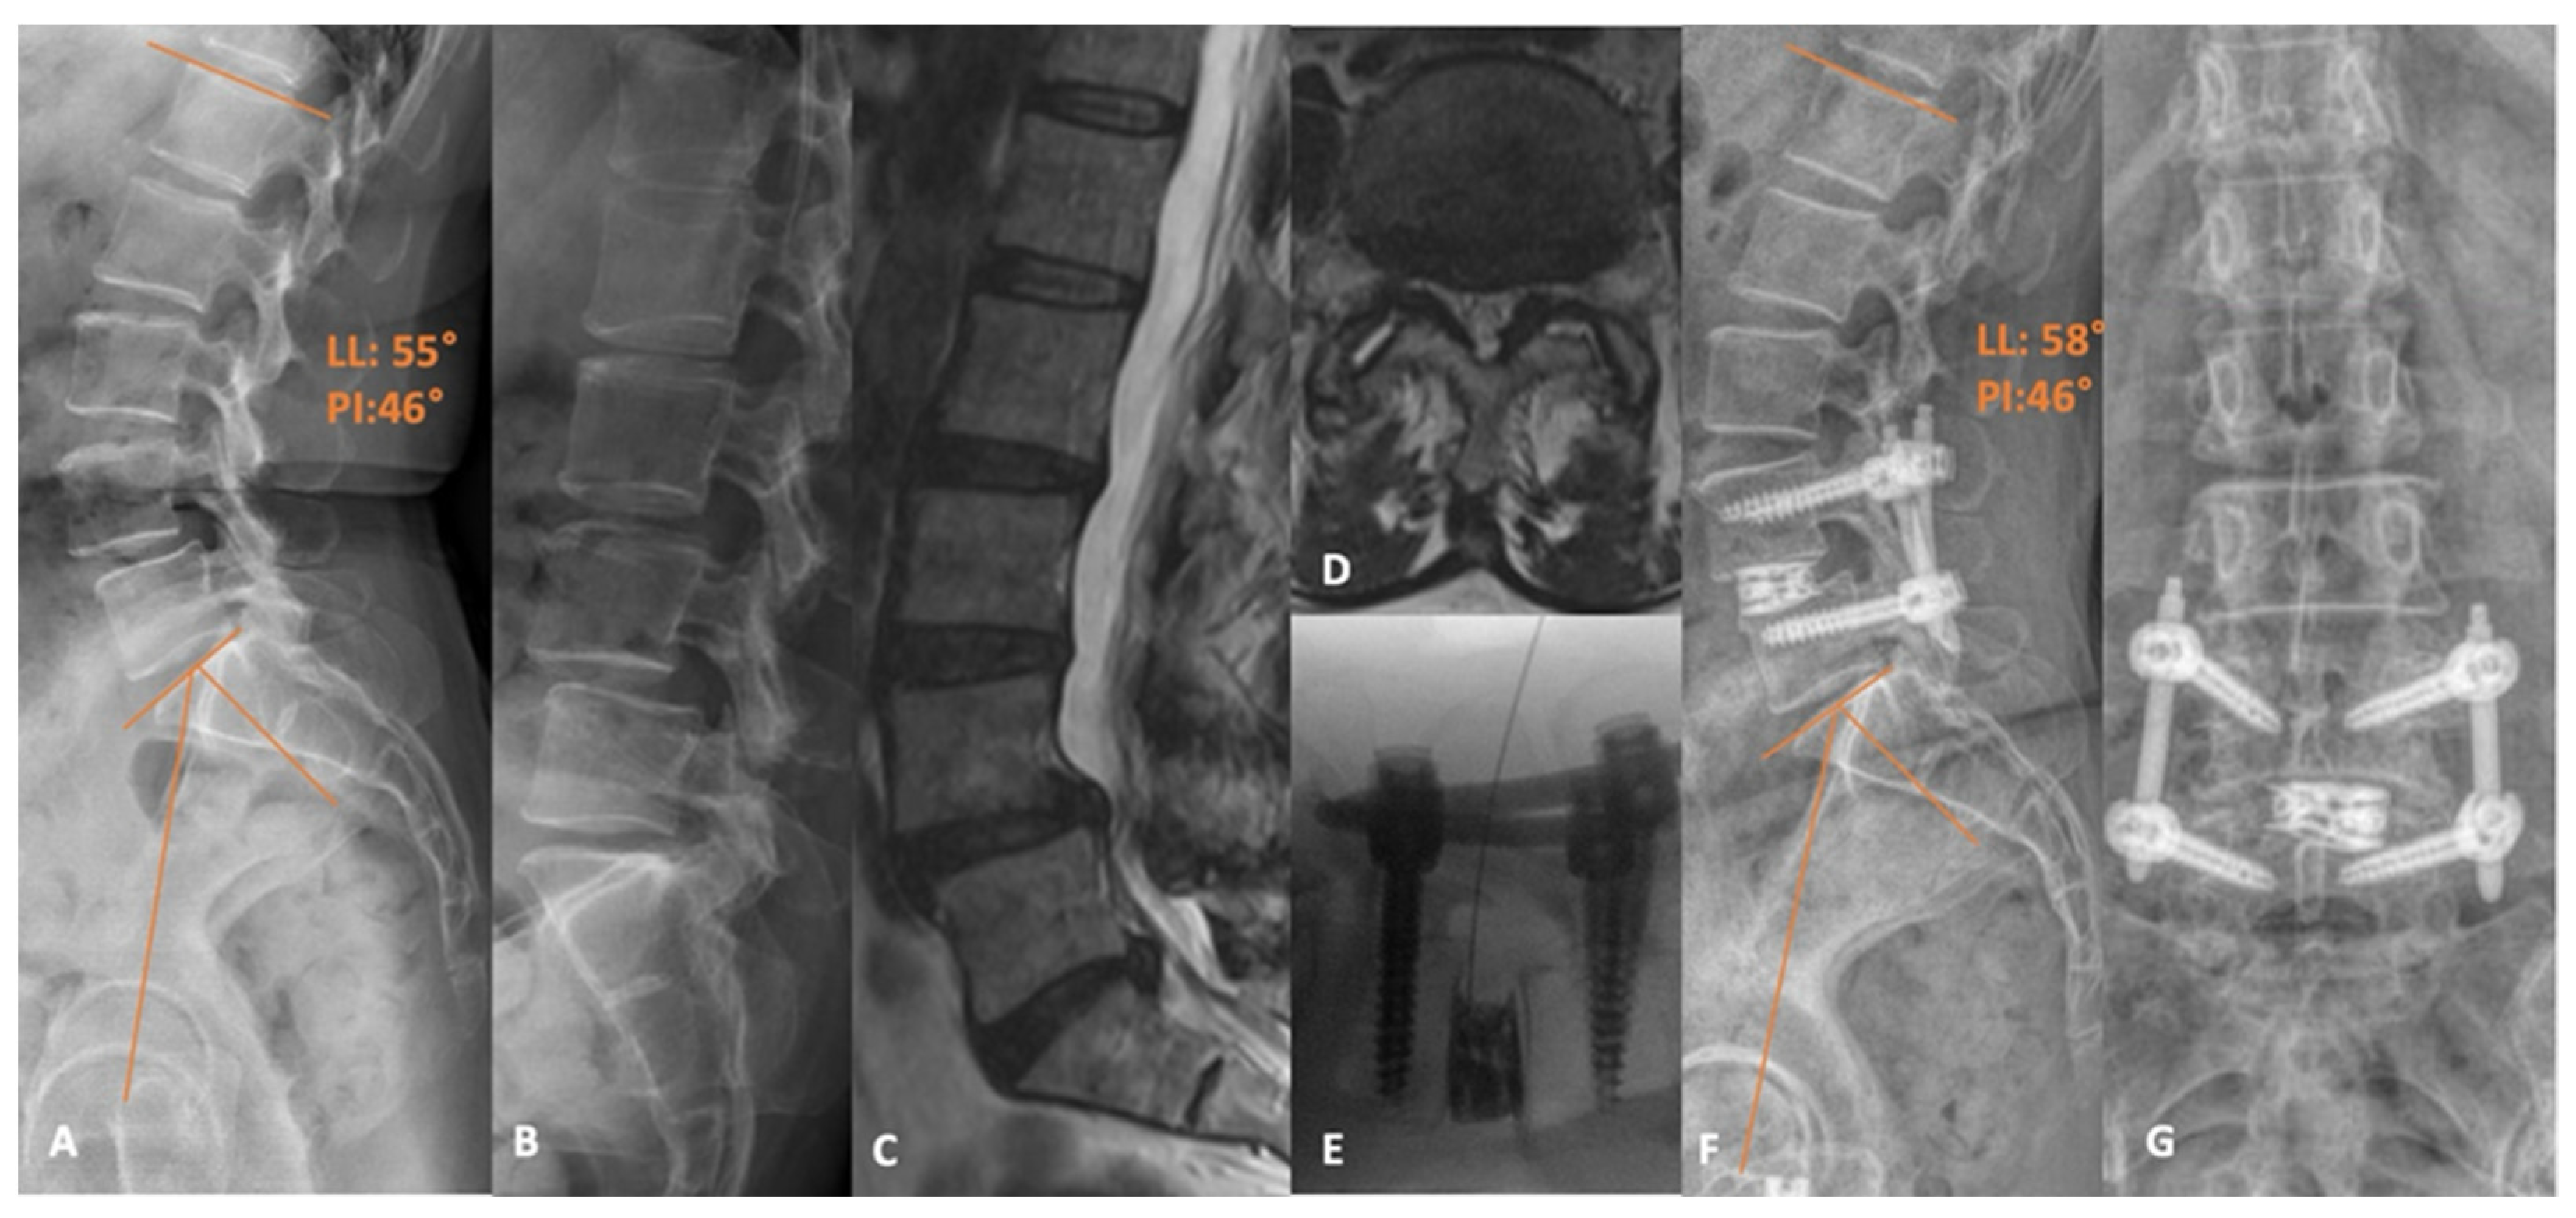

4. Minimally Invasive Transforaminal Lumbar Interbody Fusion

- Schwender, J.D.; Holly, L.T.; Rouben, D.P.; Foley, K.T. Minimally invasive transforaminal lumbar interbody fusion (TLIF): Technical feasibility and initial results. J. Spinal Disord. Tech. 2005, 18, S1–S6. [Google Scholar] [CrossRef] [PubMed]